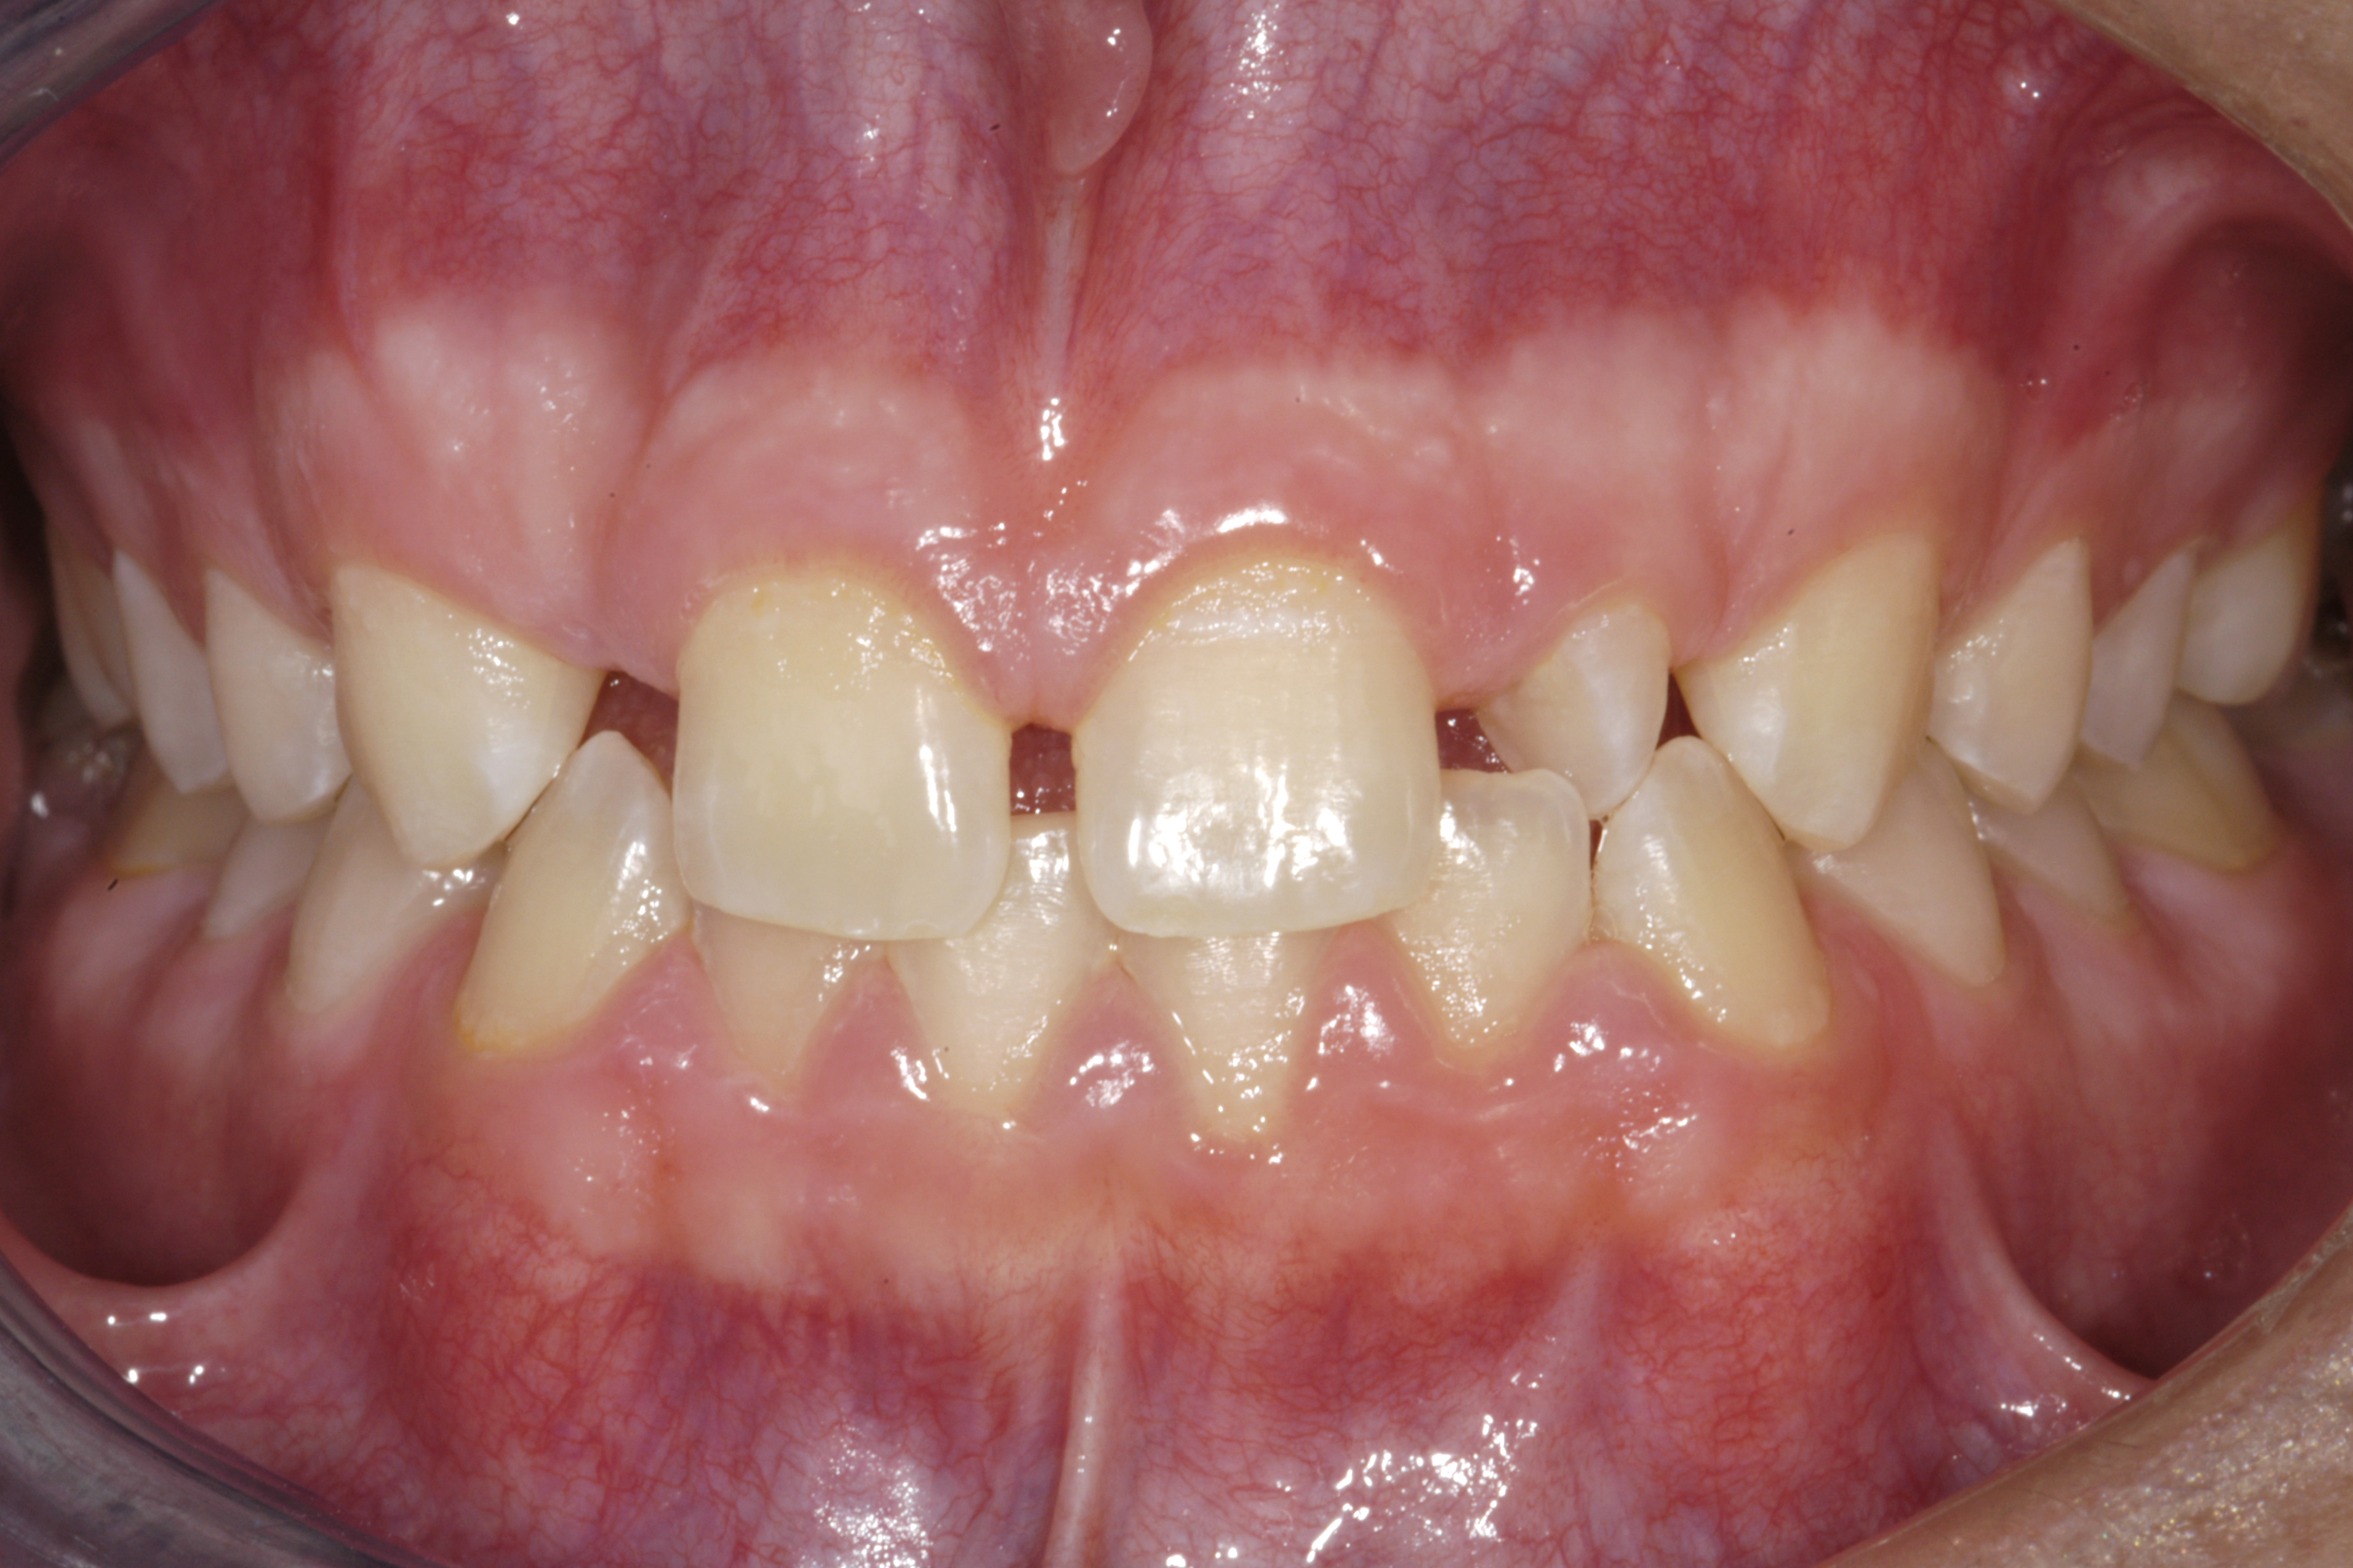

(14.) Occlusal view. Some form of augmentation would be needed if implants were being considered.

Figure 14

Some patients do not want an implant due to the need for surgical intervention, and others may not have enough space for implant placement. A 15-year-old patient presented to the office after completion of orthodontic treatment to idealize the spacing of her teeth and improve her occlusal relationship (Figure 12 through Figure 14). Because both of her maxillary lateral incisors were missing, the patient was wearing a retainer with lateral incisor pontics. She had a busy school schedule, but expressed her desire for a fixed restorative option. All of her options were discussed, and the patient was informed that if she wanted an implant, she would have to wait for at least 3 to 4 years for completion of growth. The patient was not sure if or when she wanted to have an implant placed in the future, especially considering her busy schedule and desire to attend college after high school. Considering her age and the need to be conservative, a single-wing zirconia Maryland Bridge was chosen as the ideal prosthetic replacement option. Because bonding a non-etchable and smooth surface such as zirconia requires chemical adhesion, it was decided to use a modified technique to make the bridge more retentive. One of the ways to improve adhesion of a zirconia bridge is to use an etchable feldspathic ceramic layer on the internal surface of the zirconia retainer.56-58 Unfortunately, it can be difficult to determine the thickness of the ceramic and ensure accurate seating of the restoration.

A 14-year-old patient presented to the office with his mother (Figure 1). His chief complaint involved the large spaces between the teeth created by his missing right maxillary lateral incisor and his small left maxillary lateral incisor. He desired to replace the missing tooth with an implant and create a beautiful smile. Upon examination, he was found to have a class I canine and molar relationship, but because he had a tooth size/arch size discrepancy and space distal to the right central incisor, the remaining incisors had drifted to the right. The left maxillary lateral incisor was peg-shaped and in a cross bite position. Studies have shown a clear association between congenitally missing teeth and reduced tooth size.59-62 Because he was only 14-years-old at the time and could not have implants placed until the cessation of growth (somewhere in the vicinity of 22 years old), he was sent to the orthodontist for alignment of the teeth.16,17 After 2 years of orthodontics, the appliances were removed, and his tooth coloration was improved using carbamide peroxide bleaching (Figure 2). Because some form of provisional needed to be placed until he was finished growing, a double-wing metal resin-bonded bridge was chosen. As discussed earlier, this is the ideal transitional prosthesis for patients that have congenitally missing maxillary lateral incisors. The benefits of this type of prosthesis include its ability to be removed and rebonded during the surgical phase of treatment and its ability to retain the roots in their proper position after orthodontic treatment.16 The final plan for the patient was to increase the width of the central and the maxillary left lateral incisor, utilizing porcelain laminate veneers to achieve the appropriate width/length ratio of 80%. A wax-up was created to idealize tooth size, a putty matrix was made from the wax-up to facilitate bonding of the incisors, and a non-precious, double-wing metal resin-bonded bridge was fabricated for lateral incisor replacement. Once the teeth were bonded to ideal size, the “Maryland Bridge” was fabricated from a polyvinyl arch impression with the newly bonded teeth (Figure 3). The metal frame was cast from a non-precious alloy to allow for fabrication of a very thin frame and to create a better surface for bonding. After sandblasting the internal aspect of the frame with CoJet™ silica (3M ESPE), accomplishing salinization, and executing cementation with a dual-cure resin cement, a fairly good adhesion to the frame was anticipated.29 The enamel surface was etched with phosphoric acid for 30 seconds, the primer (Single Bond Plus, 3M ESPE) was applied to both the internal surface of the sandblasted framework and the etched enamel, and the bridge was cemented with RelyX™ ARC (3M Espe) dual-cured resin cement (Figure 4 and Figure 5).